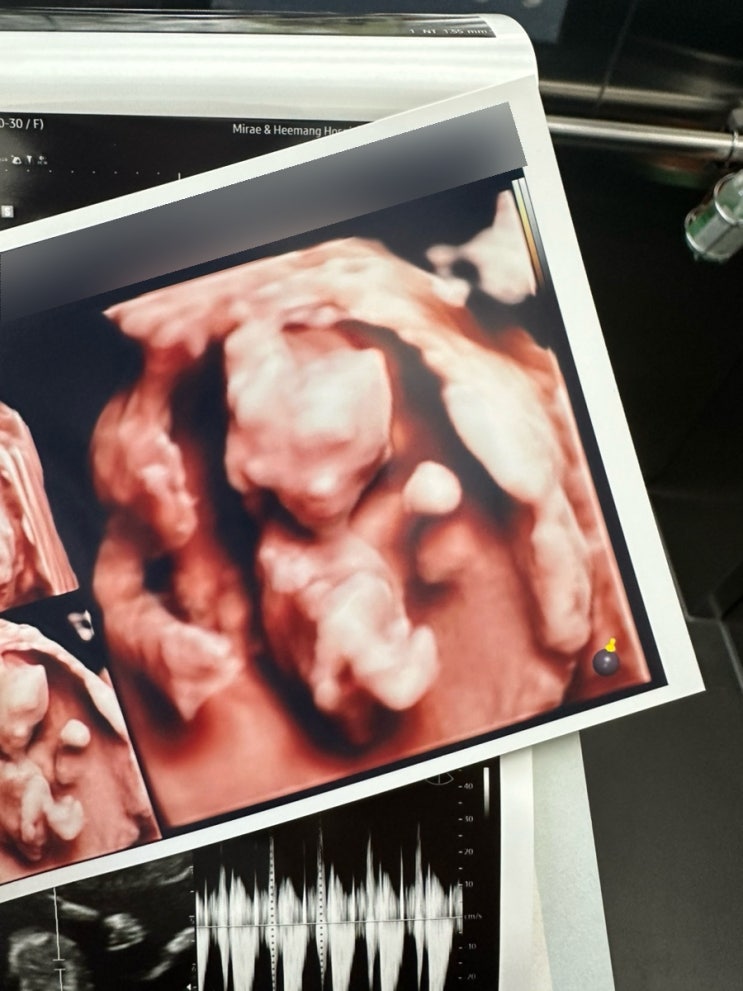

[임신 12주차]증상,드디어 첫 정밀초음파, 성별❣️

엘디와 함께한지 벌써 12주 째! 안정기 시작으로 불리우는 주수이고 나는 드디어!!! 크녹산과 이별했다~~~ ...